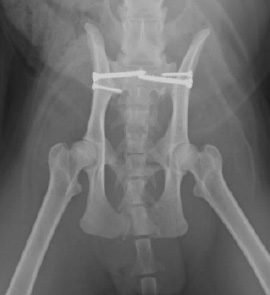

股関節脱臼

治療法

治療方法の選択肢は内科的治療と外科的治療がありますが、股関節が脱臼してしまうと、関節の構造がもとには戻りません。関節が亜脱臼のような不安定な状態だと、骨関節炎に進行したり、再脱臼を起こしてしまいます。当院では股関節脱臼の多くの場合において、外科的治療を選択しています。

- 内科的治療の場合・・・

- TVレントゲン透視下で脱臼を整復し、包帯固定(エーマースリング)を行う。

- 外科的治療の場合・・・

- 当院では大腿骨頭骨頚切除(FHO)を第一選択としております。